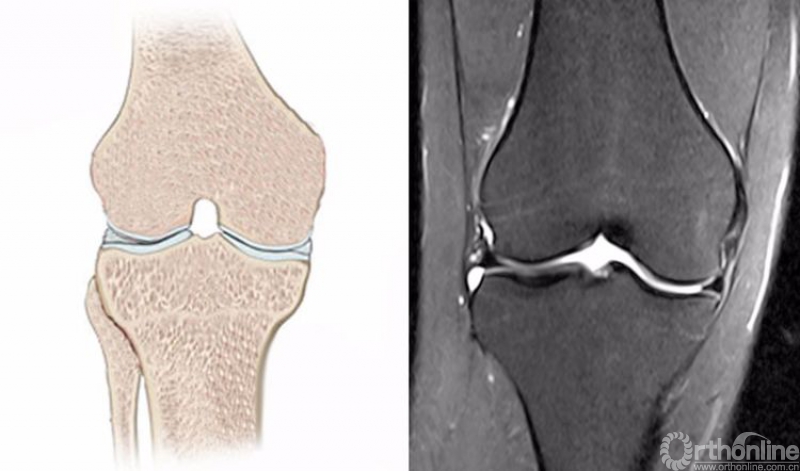

正常的膝关节进行MRI扫描时,不管任何一个序列,其骨髓信号一般T1WI呈均匀一致的灰色,T2WI及STIR呈均匀一致的黑色。

1.膝关节冠状位的正常MRI图像